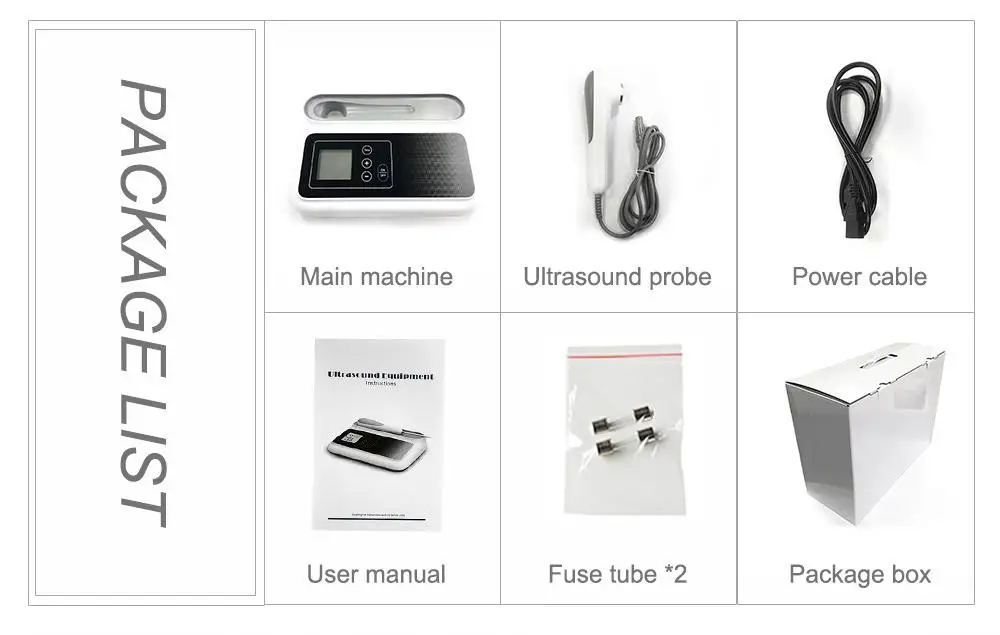

Standard Configuration:

-Main Host(probe) 1 Unit

-Internal Battery and charger 1 Set

-Non-slip lanyard